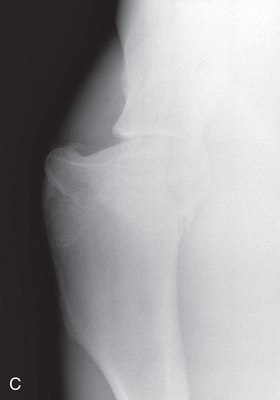

Shoulder Optional views | Mediolateral (ML) | Lateral (L) |

| Cranioproximal 45-degree medial–caudodistolateral oblique (CrPr45M-CaDiLO) | CrMCdLO | |

| Cranioproximal 45-degree lateral–caudodistomedial oblique (CrPr45L-CaDiMO) | CrLCdMO | |

To attain quality projections of the shoulder joint, the use of general anesthesia and placement of the patient in lateral recumbency are recommended. The standing position may be possible if the patient tolerates manipulation. The easiest and maybe only view of the shoulder that can be obtained is the mediolateral.